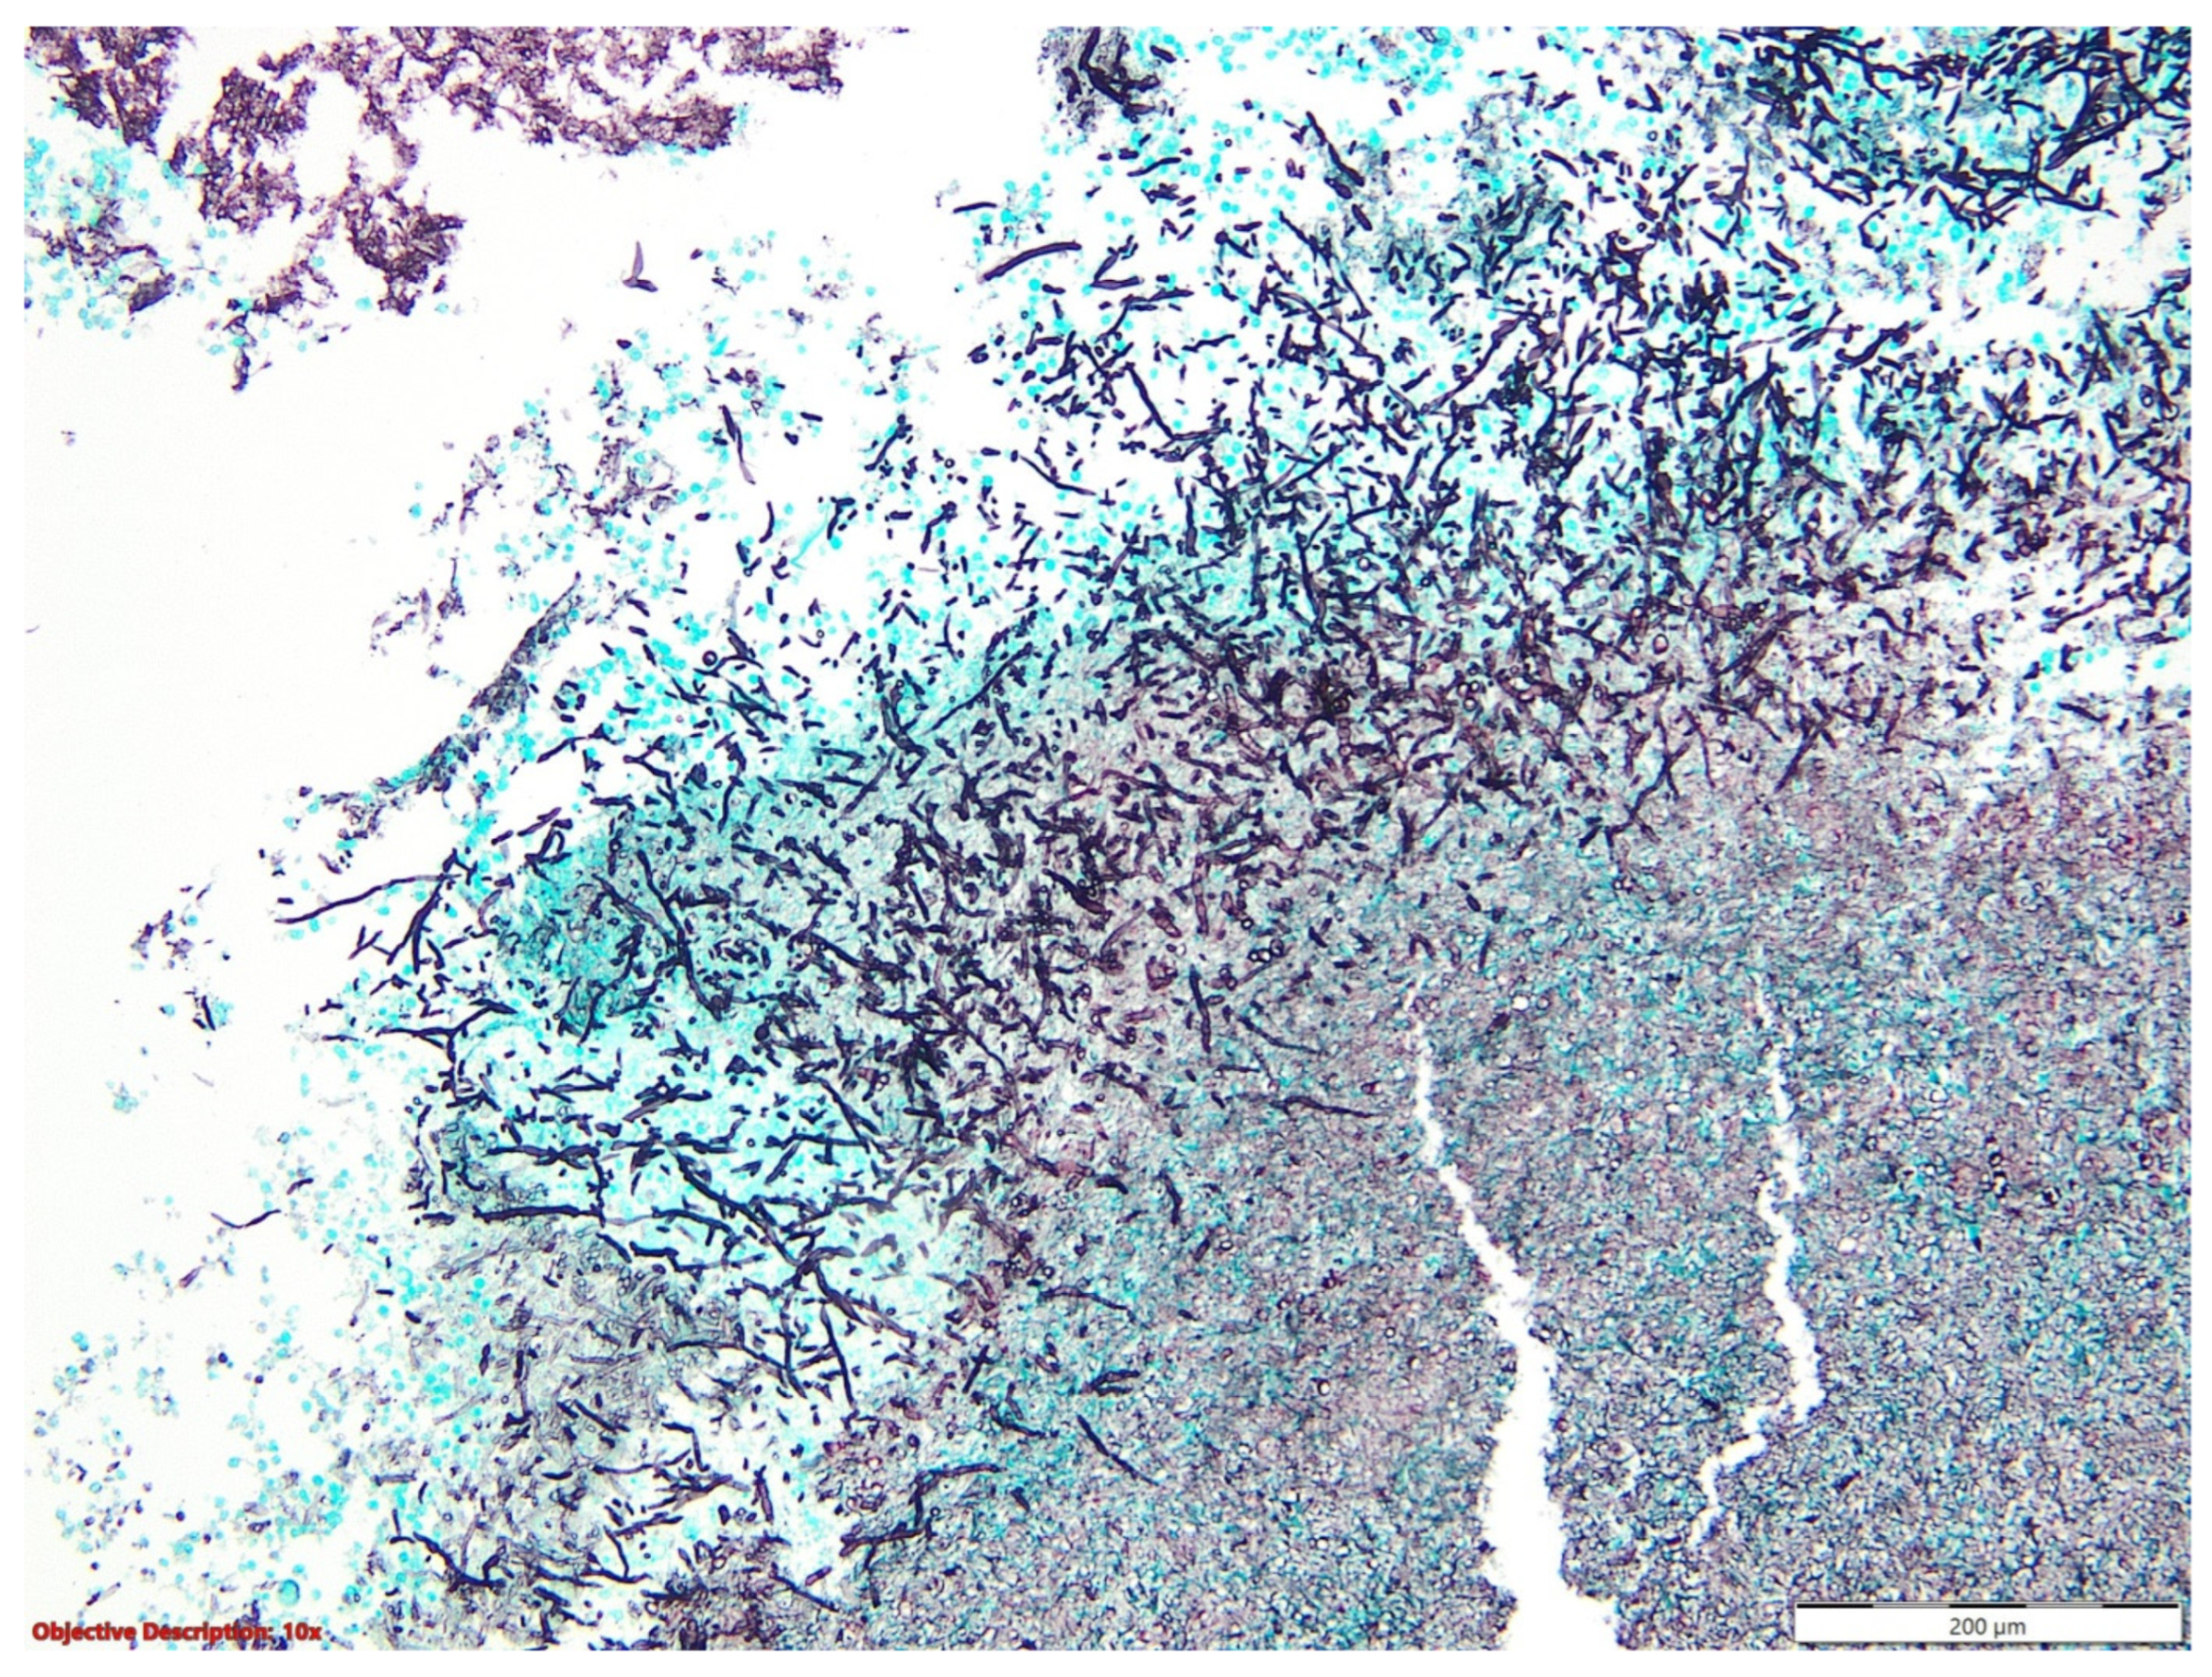

3.1. Case No. 1

3.2. Case No. 2

3.3. Case No. 3

3.4. Case No. 4